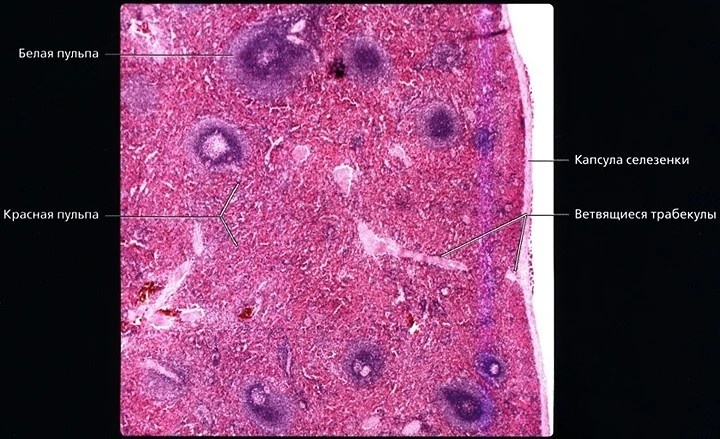

Гистологическое строение

Селезенка покрыта фиброэластической капсулой, от которой внутрь отходят трабекулы, тем самым образуя каркас органа. Внутреннее содержимое разделяется на две пульпы:

• Белая пульпа состоит из лимфатических узлов, участвующих в иммунном ответе.

• Красная пульпа выполняет фильтрацию крови, удаляя старые эритроциты и тромбоциты, а также служит депо крови, которое позволяет селезенке изменять объем при необходимости.